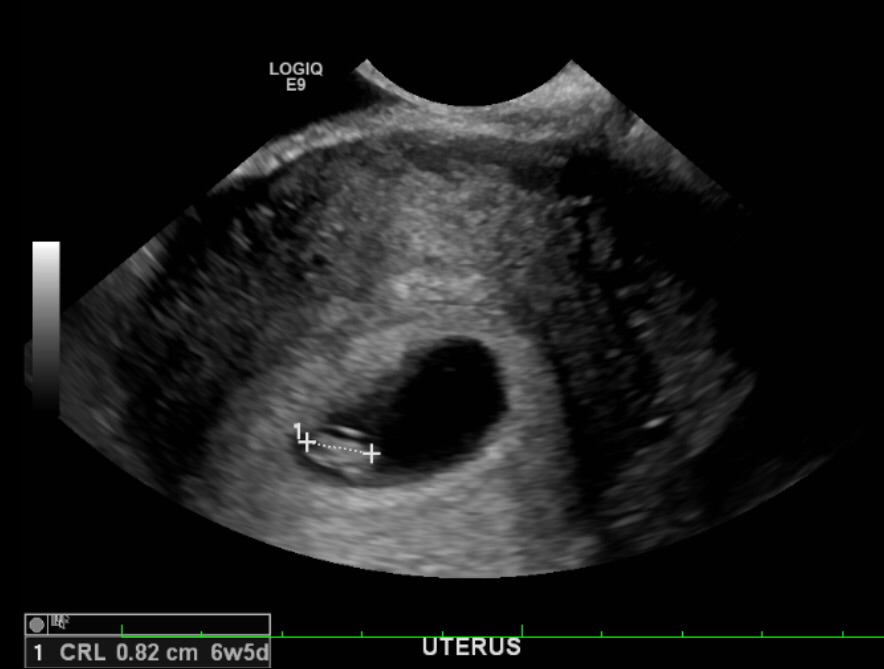

What about mine? this was at 6w6d. It was a transvaginal u/s. I'm 13 weeks now, so I'm not too far from finding out, but I am curious about this Ramzi thing. Thanks!